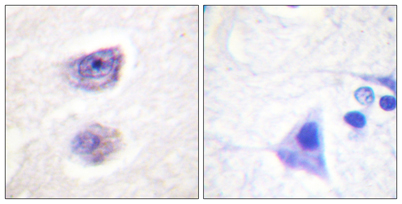

| Dilutions: | Western Blot: 1/500 - 1/2000. Immunohistochemistry: 1/100 - 1/300. ELISA: 1/5000. Not yet tested in other applications. |